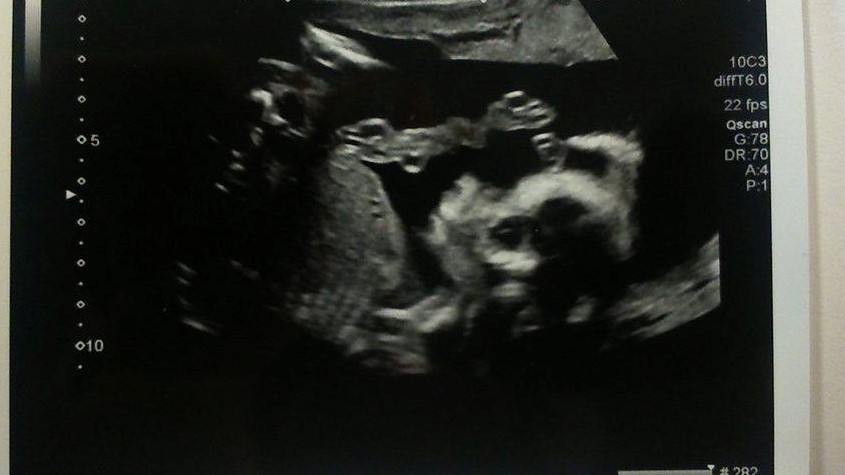

Please. Any guesses on a boy or girl please? Skull/Nub Theory?

Are there any signs at all in my scan photos about whether I'm carrying a boy or a girl?

I know they aren't the clearest photos, but they're the only ones I have.

12 weeks

Attachment 36254